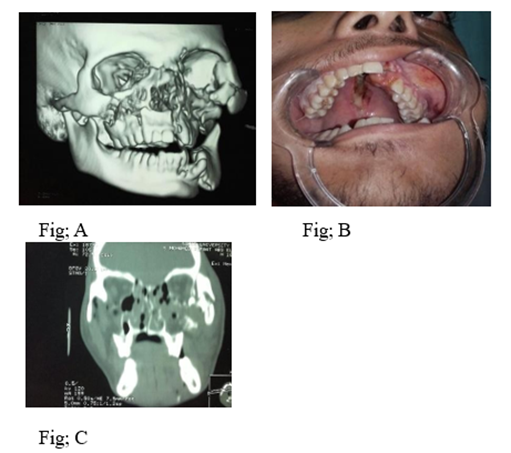

Figure 1: Preoperative View; (A) preoperative 3D CT; (B) Preoperative occlusion; (C) coronal view.

It is observed that most of bilateral panfacial fractures were due to road traffic accidents which agree with otherstudies. 5 submental intubation is safe and simple to execute without the need of any specialized instrument. We used submental intubation in 44 patients about 24.4% of cases which was very helpful as it is easy and not interfering with occlusion or fixing the nasal complex fracture. Early intervention prevents postoperative facial deformity or unacceptable results. In present study the timing of surgery is crucial as our protocol of management is to operate the patient as soon as the facial the edema subsided (from 7 to 10 days).